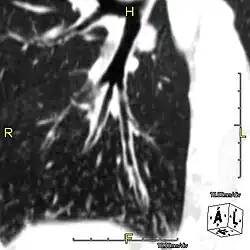

Around 80% of people with primary ciliary dyskinesia experience respiratory problems beginning within a day of birth. Many have a collapsed lobe of the lung and blood oxygen low enough to require treatment with supplemental oxygen.[1] Within the first few months of life, most develop a chronic mucus-producing cough and runny nose.[1] The main consequence of impaired ciliary function is reduced or absent mucus clearance from the lungs, and susceptibility to chronic recurrent respiratory infections, including sinusitis, bronchitis, pneumonia, and otitis media. Progressive damage to the respiratory system is common, including progressive bronchiectasis beginning in early childhood, and sinus disease (sometimes becoming severe in adults). However, diagnosis is often missed early in life despite the characteristic signs and symptoms.[2] In males, immotility of sperm can lead to infertility, although conception remains possible through the use of in vitro fertilization, there also are reported cases where sperm were able to move.[8] Trials have also shown that there is a marked reduction in fertility in females with Kartagener's syndrome due to dysfunction of the oviductal cilia.[9]

Many affected individuals experience hearing loss and show symptoms of otitis media which demonstrates variable responsiveness to the insertion of myringotomy tubes or grommets. Some patients have a poor sense of smell, which is believed to accompany high mucus production in the sinuses (although others report normal – or even acute – sensitivity to smell and taste). Clinical progression of the disease is variable, with lung transplantation required in severe cases. Susceptibility to infections can be drastically reduced by an early diagnosis. Treatment with various chest physiotherapy techniques has been observed to reduce the incidence of lung infection and to slow the progression of bronchiectasis dramatically. Aggressive treatment of sinus disease beginning at an early age is believed to slow long-term sinus damage (although this has not yet been adequately documented). Aggressive measures to enhance clearance of mucus, prevent respiratory infections, and treat bacterial superinfections have been observed to slow lung-disease progression. The predicted incidence is 1 in approximately 7500.[10]

Diagnosis

Several diagnostic tests for this condition have been proposed.[5] These include nasal nitric oxide levels as a screening test, light microscopy of biopsies for ciliary beat pattern and frequency and electron microscopic examination of dynein arms, as the definite diagnosis method. Genetic testing has also been proposed but this is difficult given that there are multiple genes involved.[6]